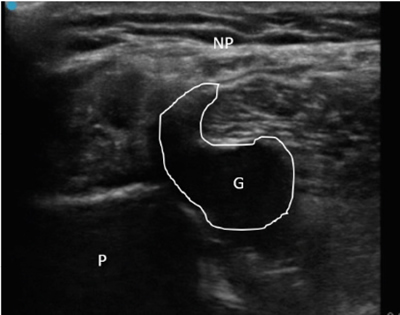

Neuropatía peronea secundaria a ganglión extraneural: revisión de literatura y propuesta de tratamiento. Caso no positivo

Este artículo presenta el caso de un paciente de 69 años con una neuropatía compresiva peronea secundaria a un ganglión, inicialmente interpretada como una radiculopatía L5. Este incorrecto enfoque supuso la sobremedicación del paciente, un mal control algésico, la realización de una discectomía L4-L5 innecesaria y una pobre evolución neurológica.

Un enfoque diagnóstico correcto y un abordaje terapéutico precoz habrían supuesto una mayor mejoría clínica e incluso una recuperación neurológica completa del paciente. Por ello, este caso sirve para resaltar: a) el valor de la ecografía en neuropatías periféricas como herramienta diagnóstica y pronóstica y el de la ecografía en gangliones como arma diagnóstico-terapéutica; b) el uso de las pruebas diagnósticas como apoyo a una exploración física exhaustiva, y no como diagnóstico en sí mismas, y c) la importancia de la publicación de casos no positivos para optimizar recursos, evitar repetir errores, reducir el sesgo de publicación y facilitar el inicio de proyectos de investigación.